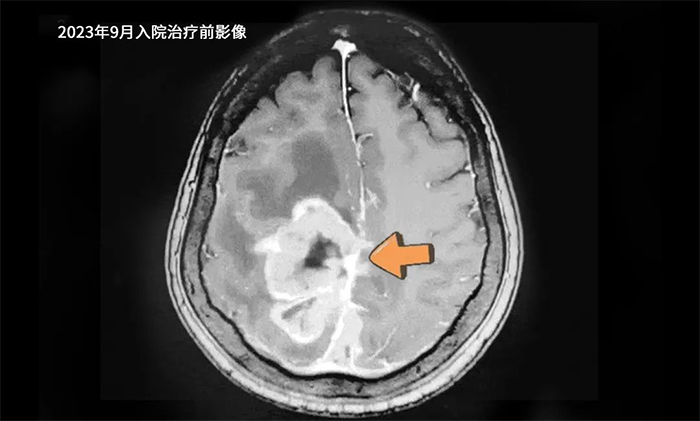

患者趙某(化名),女性,73歲。2014年因右肺腫瘤至當(dāng)?shù)蒯t(yī)院行手術(shù)切除,術(shù)后恢復(fù)良好。2023年7月,因發(fā)現(xiàn)腦轉(zhuǎn)移占位病變,于外院行開顱手術(shù),病理報(bào)告為轉(zhuǎn)移性神經(jīng)內(nèi)分泌癌。術(shù)后,左側(cè)肢體活動(dòng)障礙逐漸加重,9月復(fù)查頭顱增強(qiáng)核磁共振提示腫瘤復(fù)發(fā)。遂來我院對(duì)顱內(nèi)腫瘤病灶進(jìn)行進(jìn)一步治療。

▲ 入院治療前影像

入院時(shí)查體,受腫瘤占位效應(yīng)影響,患者左側(cè)肢體肌力0級(jí),無法自己行走,需要借助輪椅,生活自理能力大受影響。經(jīng)腫瘤科(放療)頭部伽瑪?shù)督M陳琦主任精心治療,病情明顯控制。